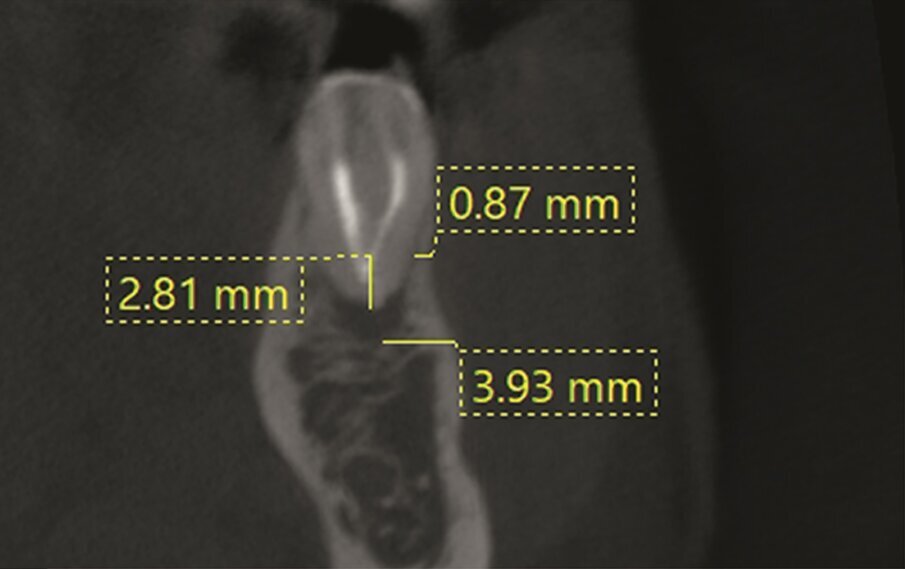

A 38-year-old female patient consulted owing to moderate pain associated with her previously treated maxillary right second premolar. Her medical history was non-contributory. Clinical examination revealed that the tooth was slightly sensitive to vertical percussion. Periodontal probing depth and mobility were within normal limits. A periapical radiograph showed the presence of a separated instrument outside of the root (Fig. 2a), and a preoperative CBCT scan demonstrated that the buccal bone plate was intact (Figs. 2b & c). Endodontic retreatment had been performed five months earlier. The diagnosis for tooth #15 was previously treated symptomatic periapical periodontitis, and the treatment of choice was guided EMS.

An intra-oral scan (TRIOS) of the maxilla, and the resulting STL file (Fig. 2d) was combined with the DICOM files of the CBCT scan to plan a surgical guide using the Zirkonzahn. Implant-Planner software (Zirkonzahn) modified with Meshmixer (Autodesk). A template that marked the limits of a cortical window to accurately reach the apical area was designed and printed (Figs. 2e & f).

The use of surgical guides for periapical surgery was first suggested by Pinsky et al. for more precise and consistent localisation of root apices. In a preclinical study, the apical mean distance of osteotomies to planned objectives was 0.79 mm (± 0.33 SD) with surgical guides and 2.27 mm (± 1.46 SD) in freehand osteotomies.4